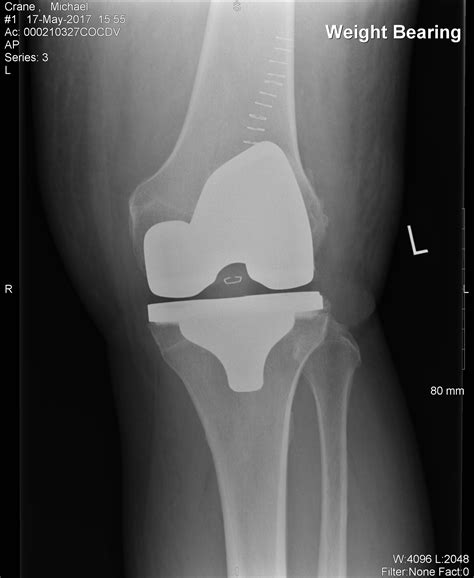

Knee Replacement Implant - 3D Model by zames1992d